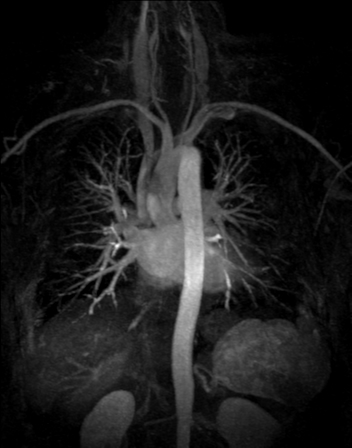

RM Cardíaca

Descripción

Es una prueba diagnóstica no invasiva que obtiene información morfológica y funcional del corazón y las estructuras adyacentes; de esta manera se pueden diagnosticar diferentes patologías congénitas y adquiridas, o bien realizar controles en pacientes con patología previa ya conocida. En la gran mayoría de casos es necesario el uso de contraste intravenoso (gadolinio) para completar el estudio, un tipo de contraste que raramente produce reacciones adversas. Durante la prueba, el técnico le pedirá varias veces que aguante la respiración durante 10-15 segundos para obtener las imágenes lo más claras posible. No se necesita preparación previa alguna por parte del paciente. La duración de la prueba es de aproximadamente 45-60 minutos. Está contraindicada en pacientes con marcapasos; el paciente debe avisar si es portador de implantes metálicos y/o clips quirúrgicos.